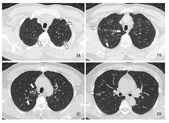

患者,男性,58岁,因"咳喘伴畏寒1周"于2020年1月17日入同济大学附属上海市第四人民医院呼吸科就诊。患者1周前无明显诱因出现咳嗽,活动后稍有气喘,无发热、咳血,无胸痛、晕厥、黑朦、心慌。血常规示:白细胞计数5.47×109个/L,血红蛋白浓度121 g/L,血小板计数168×109个/L,淋巴细胞百分比19.6%,中性粒细胞百分比72%,C反应蛋白浓度9.89 mg/L。胸部CT示:两肺多发磨玻璃影,两肺上叶明显,考虑炎性病变(见图1)。甲乙流病原体快速检测:阴性。门诊予以头孢西丁和左氧氟沙星抗炎治疗,后患者于急诊继续用药近2周。患者于1月31日再次于呼吸科门诊复诊,自觉仍有咳嗽,活动后气促明显。复查血常规示:白细胞计数8.7×109个/L,淋巴细胞百分比10%,中性粒细胞百分比83.9%,C反应蛋白浓度159.25 mg/L。甲乙流病原体快速检测:阴性。胸部CT示:两肺大片炎症,较2020年1月17日明显进展,病毒性肺炎可能(见图2)。患者否认发病前14 d旅游外出史,否认接触疫区有发热或呼吸道症状的患者,否认聚集性发热。自诉1月19日有外出打麻将行为,否认牌友有发热,但牌友的具体流行病学史不详。因此考虑患者有感染新型冠状病毒肺炎可能,予以发热门诊留观病房隔离观察,并采集上呼吸道、下呼吸道、血液标本进行新型冠状病毒核酸检测。